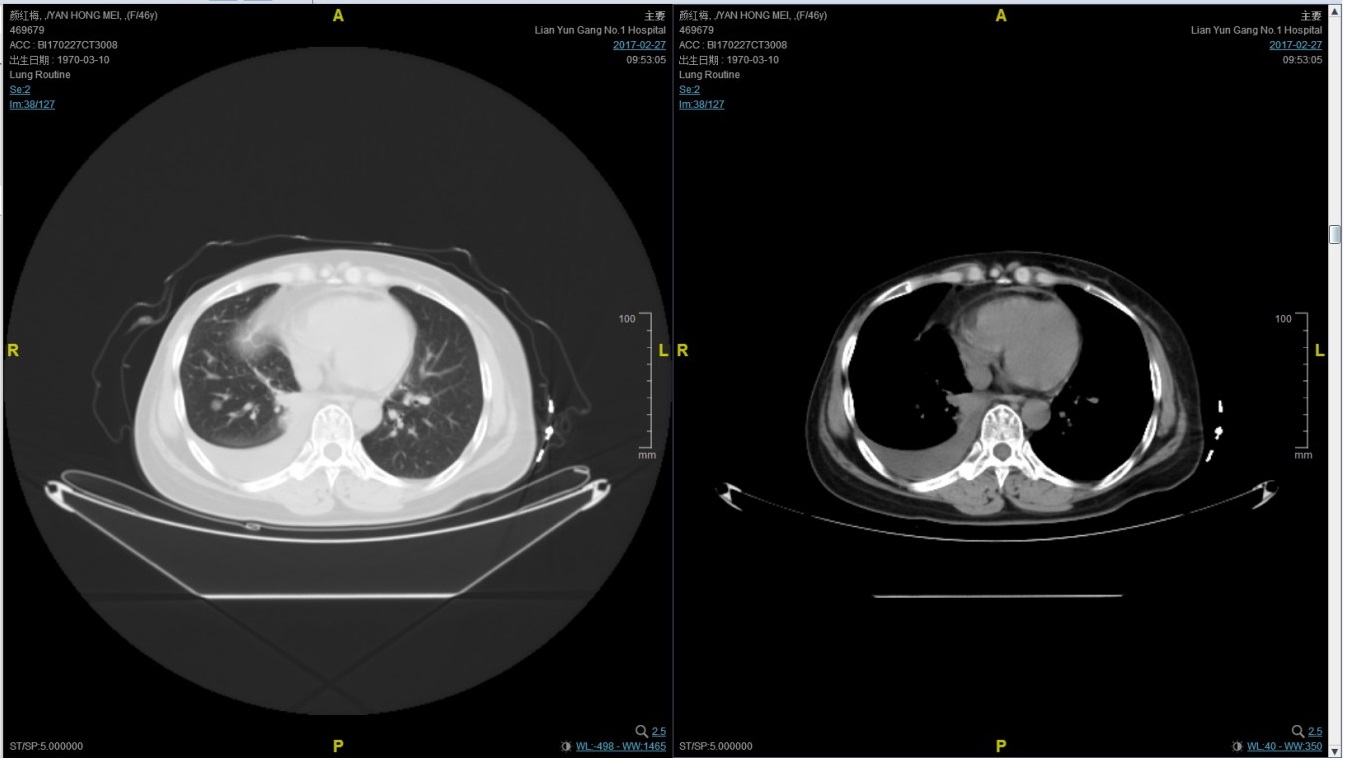

2017-02-27患者因气喘胸闷再次就诊。患者肺部病灶进展,同时出现肝脏转移。再次给予曲妥珠单抗+长春瑞滨化疗一周期,效果不佳,推荐换用TKI治疗,患者放弃治疗。PFS3=12个月。

患者颜X X,女,发病年龄43岁。2010.12.01因体检发现右乳质硬、无痛性肿块住院治疗。入院查体肿块约2.5cm × 1.5cm。考虑诊断为右侧乳腺癌。2010.12.06在我院全麻下“右乳癌改良根治术”。术后病理:(右)乳腺浸润性导管癌,组织学分级Ⅲ级;乳头、皮肤未见癌累及,同侧腋窝淋巴结转移(19/19)。免疫组化:ER(-),PR(-),C- erbB-2(3+)。术后诊断右乳浸润性导管癌并右侧腋窝淋巴结转移(pT2N3M0,IIIC期,HER2阳性型)。术后于2011-01-06起在连云港市第一人民医院给予AC方案化疗4周期,2011-03-20给予右胸壁+右锁骨上下淋巴引流区放疗Dt50Gy/25f,2011-05-26予TH方案化疗4周期(曲妥珠单抗d1首次480mg,以后360mg)共4周期。后续予以曲妥珠单抗360mg(每21天为一周期)维持治疗1年,末次使用曲妥珠单抗的时间在2012年5月,后定期随访,病情稳定。2013-11-23全面复查发现肺转移。 DFS=35个月。2013-11-26起给予曲妥珠单抗(440mg d1)/脂质体紫杉醇(240mg d2)/CBP(500mg d2)方案化疗一个周期,出现Ⅱ度骨髓抑制,因患者主诉乏力明显,后修改方案曲妥珠单抗(330mg 每 3周重复)/脂质体紫杉醇(120mg d1+d8+d15,每4周重复)化疗,化疗过程顺利,患者无明显骨髓抑制,无乏力主诉,于2014-02-11全面复查,疗效评价为PR。继续曲妥珠单抗+脂质体紫杉醇(共六周期)治疗,疗效评价CR。后续予以曲妥珠单抗维持治疗,随访病情稳定。2015年4月,患者肺部病灶复发。给予曲妥珠单抗+希罗达治疗(希罗达1500mg,一天两次口服)。PFS1=17个月。2016-2-18,肺部病灶进展,肺内转移病灶增多。PFS2=10个月。从2016-2-19开始给予紫杉醇+曲妥珠单抗治疗,紫杉醇240mg,3周重复,曲妥珠单抗330mg三周重复。患者末次应用曲妥珠单抗和紫杉醇时间为2016-6-24,紫杉醇共应用4周期。CT评价SD。继续曲妥珠单抗维持治疗,且自服中药。2017-02-27患者因气喘胸闷再次就诊。患者肺部病灶进展,同时出现肝脏转移。再次给予曲妥珠单抗+长春瑞滨化疗一周期,效果不佳,患者放弃治疗。PFS3=12个月。